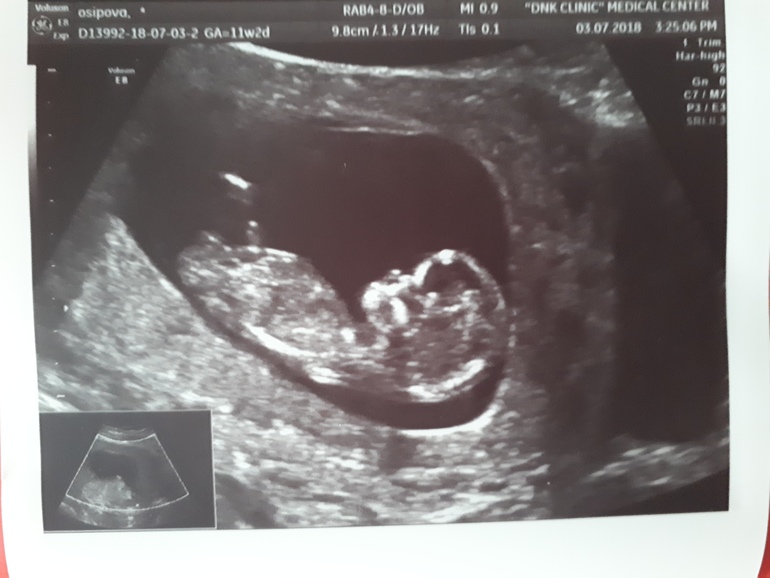

Фото со скрининга? Пол.

вроде выбрала кадры из видео, на которых что-то видно. Узист вчера сказала, что с большой вероятностью девочка. Срок 12,5 нед. Как думаете это действительно барышня?

По-моему, на фото 00:24 четко видно, что ДА. На остальных я не увидела, ноя плохо понимаю по нечетким картинкам УЗИ. Поздравляю Вас с доченькой.